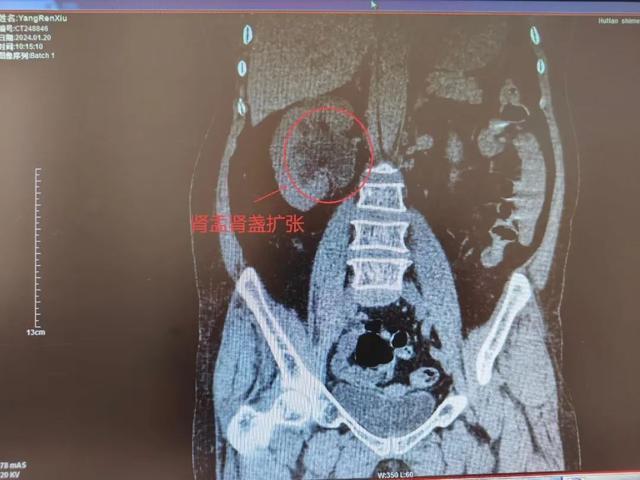

杨阿姨,66岁老年女性,因反复右侧腰腹部疼痛多次在外院治疗,但疗效均不佳。长期病痛折磨也导致患者郁郁寡欢。经熟人介绍到泌尿外科就诊,入院后完善术前检查,行右侧经皮肾穿刺造瘘,术后泌尿系造影提示:右侧输尿管末端狭窄。

术后2月拔除输尿管支架,复查双肾CT:右肾无积水;右侧输尿管无扩张。该手术不仅创伤小,患者痛苦小,恢复快,而且抗返流效果好,可代替开放手术。